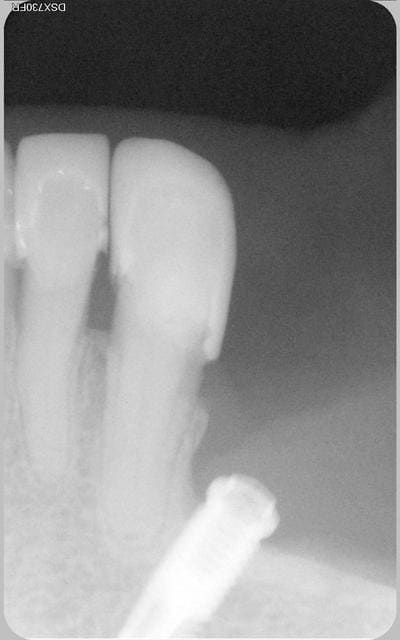

implant posé trop près d'une dent saine

La patiente revenait de l'implantologiste. Je fais une radio de control et je vois ca. La patiente refusait toute prothèse.

Voilà le bébé

La patiente est revenue pour un soin a faire sur 35 qui est bien vivante.

Satisfaite de son coeff masticatoire.

cela fait excactement 9 ans, que l'implant a été posé.

Bien sur et c'est évident que le confrére implanto ne ferait plus ca maintenant.

La nature a bon dos parfois